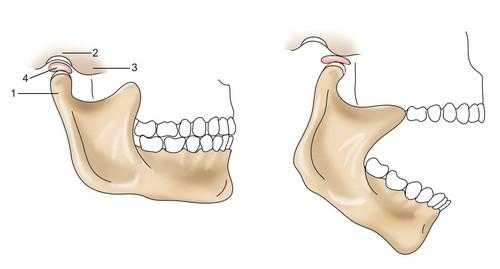

Во время движения нижней челюсти происходит сагиттальное, вертикальное и трансверзальное смещение её головок.

Вертикальное смещение необходимо для открывания и закрывания рта. При этом движение, в зависимости от силы, происходит с различной силой, определяющей степень движения головки.

Сагиттальной осью смещения называется возможность движение нижней челюсти вперед-назад. При этом, движение челюсти вперед и биомеханизм головки суставной части в момент движения называется сагиттальным путем суставов.

Трансверзальным называется возможность челюсти двигаться влево или вправо. При этом происходит движение определенных групп мышц. Например, направление жевательного аппарата вправо обуславливает левое направление латеральной мускулатуры, и наоборот.

Височно-нижнечелюстной сустав (ВНЧС) — это синовиальный сустав, и он является единственный истинным суставом в челюстно-лицевой области. Он также известен как нижнечелюстной сустав, либо как черепно-нижнечелюстное сочленение. Височно-нижнечелюстной сустав является уникальным в связи с его вращательными (гинглимоидный сустав) и поступательными (артроидальный сустав) движениями во время функционирования нижней челюсти, включая открывание и закрывание рта, жевание и речь. Правый и левый суставы не могут двигаться независимо друг от друга, так как они соединяются через нижнюю челюсть, образуя двухмыщелковое сочленение (Alomar et al. 2007). Более того, зубы служат направлением и ограничивают определенные движения нижней челюсти. Как следует из названия, в образовании височно-нижнечелюстного сустава участвуют две кости, то есть височная кость и нижняя челюсть (Рисунок 1, 2, 3, и 4 ).